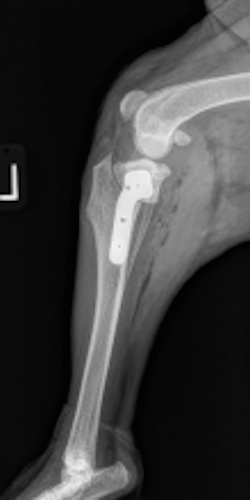

An osteotomy is a surgical cut in a bone. In the cruciate deficient stifle, a cut is made in the top of the tibia. The top portion of bone that contains the articular surface is rotated to level it. The two pieces of bone are held in place with a metal plate and screws.

Post Surgical Radiographs

While the patient is still anesthetized, the patient is taken into radiology for post-surgery radiographs (X-rays). The radiographs are assessed to measure the new tibial plateau angle. We are aiming for 5-6 degrees relative to the long axis of the tibia. The apparatus (plate and screws) are assessed for size and appropriate position.